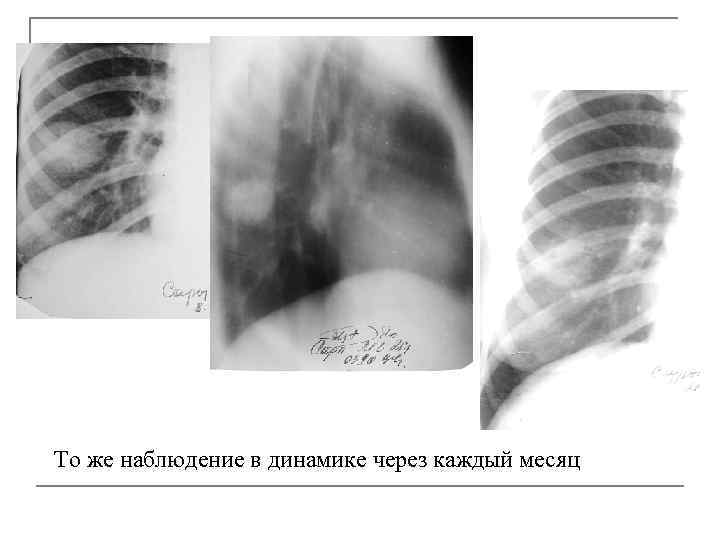

Инфильтративный туберкулез нижней доли правого легкого, фаза распада

То же наблюдение в динамике через каждый месяц